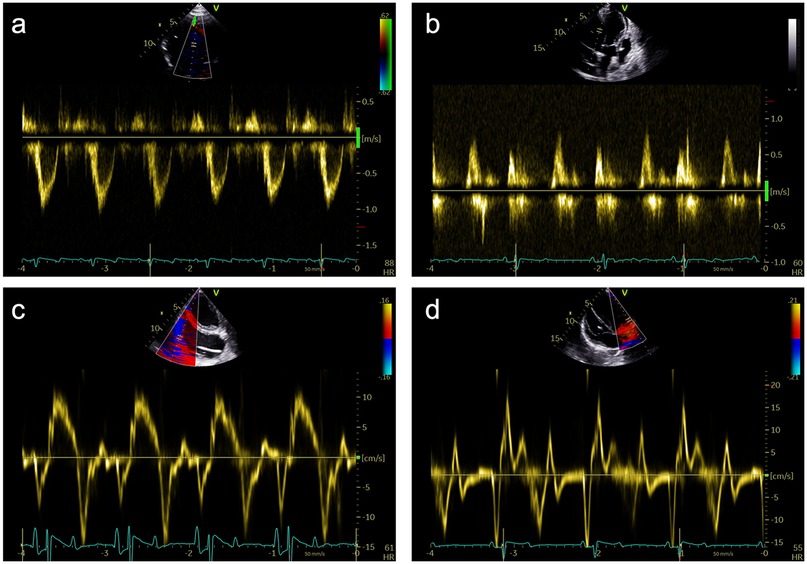

Figure 3

Four panels labeled a, b, c, and d depict echocardiographic Doppler recordings. Each panel shows the velocity of blood flow waveforms with variations in amplitude and frequency over time. Panels a and c include color maps representing blood flow direction. The ECG traces are visible below the waveforms, indicating heart rate variations. Diagrams feature velocity scales to the right, showing different measurement units.

Figure 3. Representative pulsed-wave Doppler (PWD) and tissue Doppler (TD) measurements that were obtained during subxiphoid echocardiography of 18 female German landrace swine. (a) PWD measurements in the left ventricular outflow tract in an apical 5-chamber (A5C) view. (b) Assessment of the mitral inflow profile by PWD in an apical 3-chamber view (A3C). (c) Assessment of the tricuspid annular plane systolic velocity (TASV) by alignment of the TD beam with the lateral tricuspid annulus in a right ventricular focused A5C view. (d) Assessment of the lateral mitral annular plane diastolic velocity (E’) by alignment of the TD beam with the lateral mitral annulus in an A5C view.

The examination started with an apical 5-chamber (A5C) view. The ultrasound transducer was therefore placed subdiaphragmatically, with the probe marker oriented laterally to the left (90°–110°) and tilting slightly anteriorly (10°–20°). Due to the anatomical configuration of the swine heart, a standardized 4-chamber view is rarely obtainable. Instead, the long axis of the porcine heart extends obliquely from right to left and from posterior to anterior. This modified view allowed for clear visualization of both ventricles, although the atria could be only partially visualized (Table 1). Importantly, the left ventricular outflow tract (LVOT), the aortic valve (AV) and root can be adequately visualized in a manner analogous to a human 5-chamber view. To enhance the echocardiographic evaluation, lateral or medial adjustments of the focus improved the visualization of both ventricles, facilitating volumetric measurements and speckle-tracking analysis. Additionally, proper alignment of the Doppler beam enabled valid Doppler echocardiographic assessment of the AV and the LVOT (Figure 3).

In the RV-focused apical 5-chamber view (A5C-RV), the transducer was tilted anteriorly and rocked medially to optimize the visualization of the RV (Table 1). The view focuses on the RV and the tricuspid valve (TV) with partial visualization of the LV. This view was used for detailed evaluation of RV anatomy and function, including the RV free wall longitudinal strain, right ventricular basal diameter, tricuspid annular plane systolic excursion (TAPSE), and tricuspid annular systolic velocity (TASV) (Figure 3). In addition, the tricuspid valve (TV) could be assessed by Doppler echocardiography in this view.

Valve function was assessed in detail. The aortic valve was evaluated in the A3C and A5C views, with measurements including mean and peak pressure gradients (MPG and PPG) and maximum velocity (AV Vmax). The mitral valve was examined in the A2C or A3C views, with early diastolic flow velocity (E), late diastolic flow velocity (A), E/A ratio, and deceleration time of the E-wave. Tissue Doppler imaging (TDI) was performed at the tricuspid annulus, septal wall and mitral annulus in the A5C view to measure regional myocardial tissue velocities.